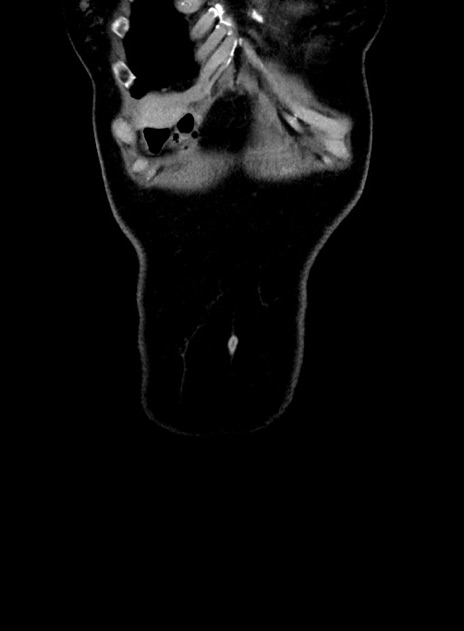

症例9(冠状断像)

【症例】 60歳代女性

【主訴】むかつき、みぞおちの痛み

【現病歴】3日前よりむかつきがあり、食事がとれない。

【既往歴】糖尿病

【身体所見】発熱なし、心窩部圧痛軽度あるも、腹膜刺激症状なし。

【データ】WBC 7400、CRP 1.92